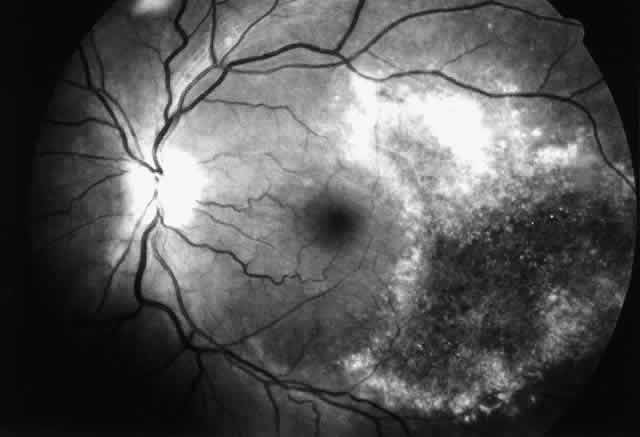

The histopathologic characteristics of AIDS-related CMV retinopathy in one autopsy study are listed in Table 3.9 CMV retinopathy frequently begins adjacent to retinal vessels in the posterior pole (Fig. 2). It is believed that virus reaches the eye via the bloodstream. Untreated CMV retinopathy in patients with AIDS is a relentlessly progressive disease. Usually, infection begins with an isolated focus of disease; rarely are there more than two or three discrete areas of infection within the eye. These lesions invariably enlarge to involve additional retinal tissue. New lesions develop less frequently. The enlargement of lesions does not progress at the same rate from all lesion borders.21 The rate of progression is faster in an anterior direction toward the ora serrata than in a posterior direction toward the fovea. CMV retinopathy has been considered a “foveal-sparing” disease. In a series of organ transplant patients with CMV retinopathy reported by Egbert and associates prior to the AIDS epidemic, only 3 of 21 eyes had macular involvement.14 The higher incidence of macular involvement in early autopsy series of patients with AIDS may reflect the fact that progression of CMV retinopathy into the macular region could not be stopped prior to the introduction of ganciclovir and foscarnet therapy. Even though the fovea can eventually be destroyed, it is usually the last area to become infected; in some cases the disease appears to move circumferentially around the fovea (Fig. 3). Eventually the entire retina will be destroyed, usually within a 6-month period.19 Progression of the retinopathy halts abruptly at the ora serrata.9 Following total retinal necrosis, it is replaced by a thin gliotic membrane.19 No virus can be identified in ocular tissue at this late stage.

Fig. 3. Cytomegalovirus retinopathy in the left eye of a patient with AIDS. Disease has reactivated at lesion borders, and the posterior border is advancing in a circumferential manner around the fovea.